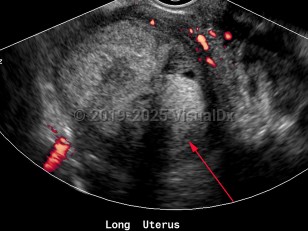

Endometrial carcinoma

Endometrial carcinomas are more common in women of European descent and more likely to develop after menopause.

Most commonly, endometrial carcinoma develops in conditions that expose the uterus to estrogen, either for very prolonged periods of time, without opposing progesterone, or both. As such, obesity, polycystic ovarian syndrome (PCOS), diabetes mellitus type 1 and type 2, anovulation, nulliparity, tamoxifen use (in postmenopausal woman), prolonged hormone replacement therapy with estrogen alone, and early menarche or late menopause are all variably potent risk factors for endometrial carcinoma.